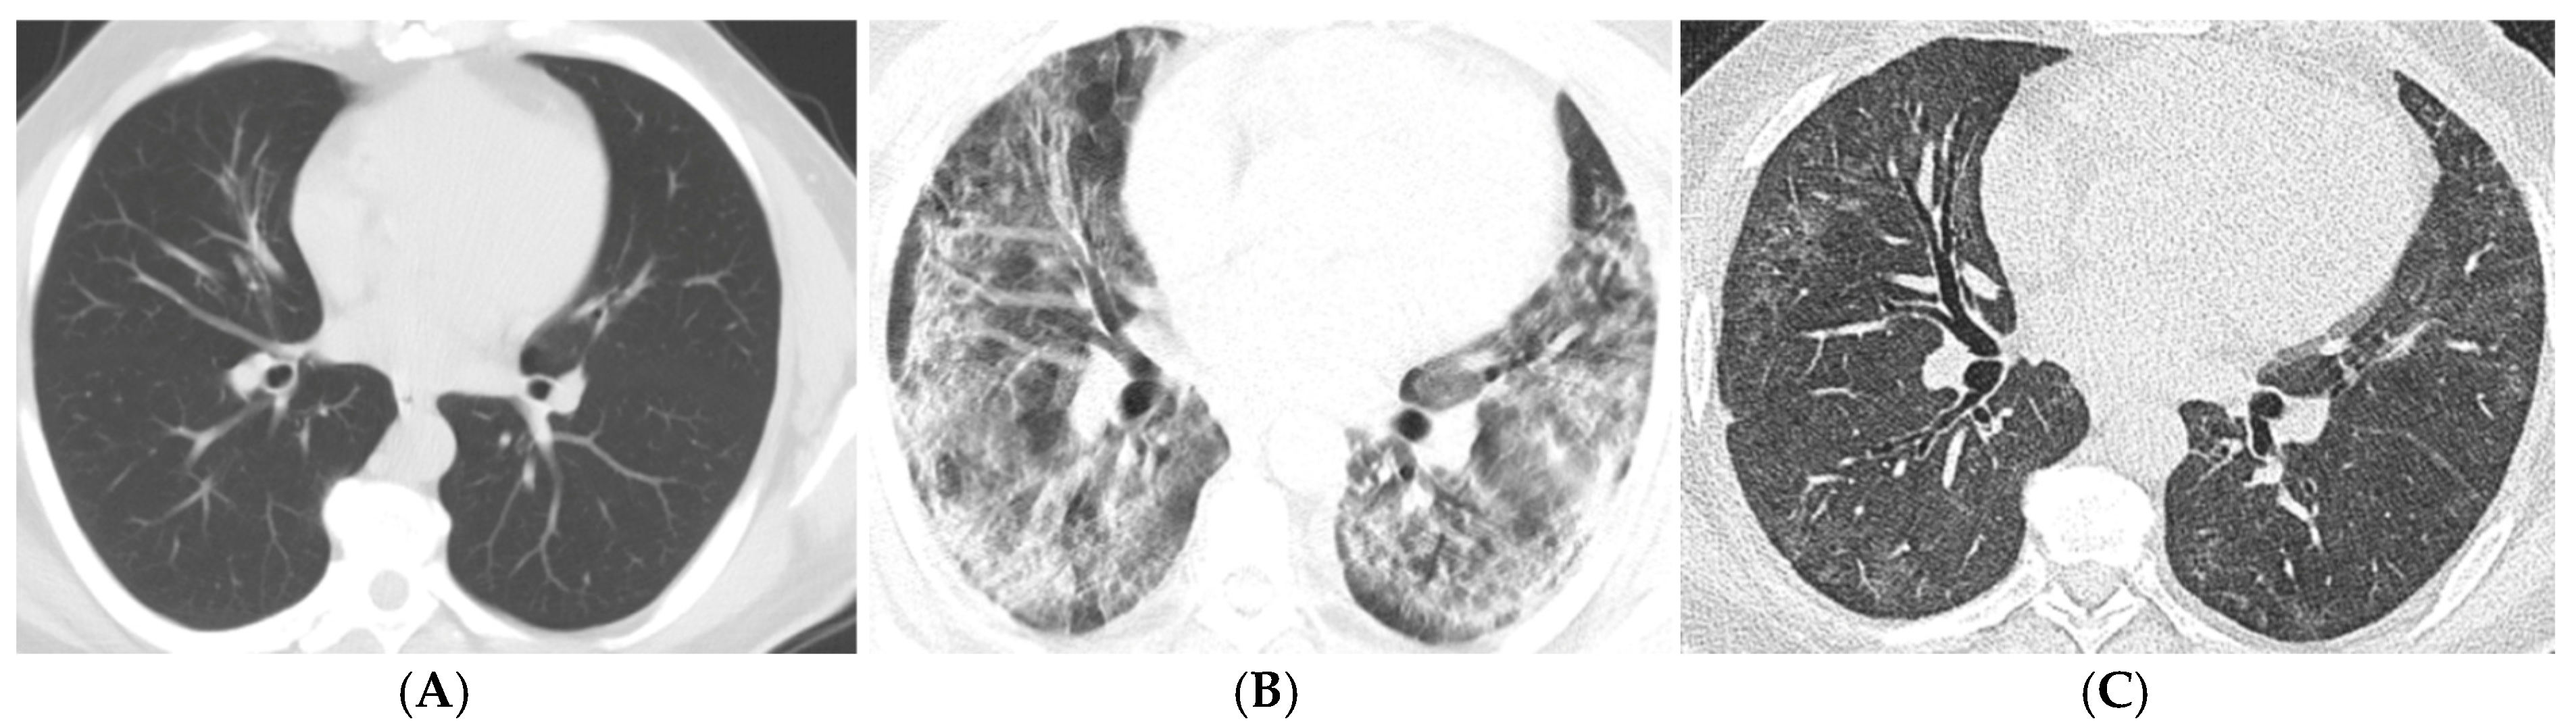

| Imaging Findings (3–6 Months) | Common Findings | Ground-glass opacities, parenchymal bands, traction bronchiectasis |